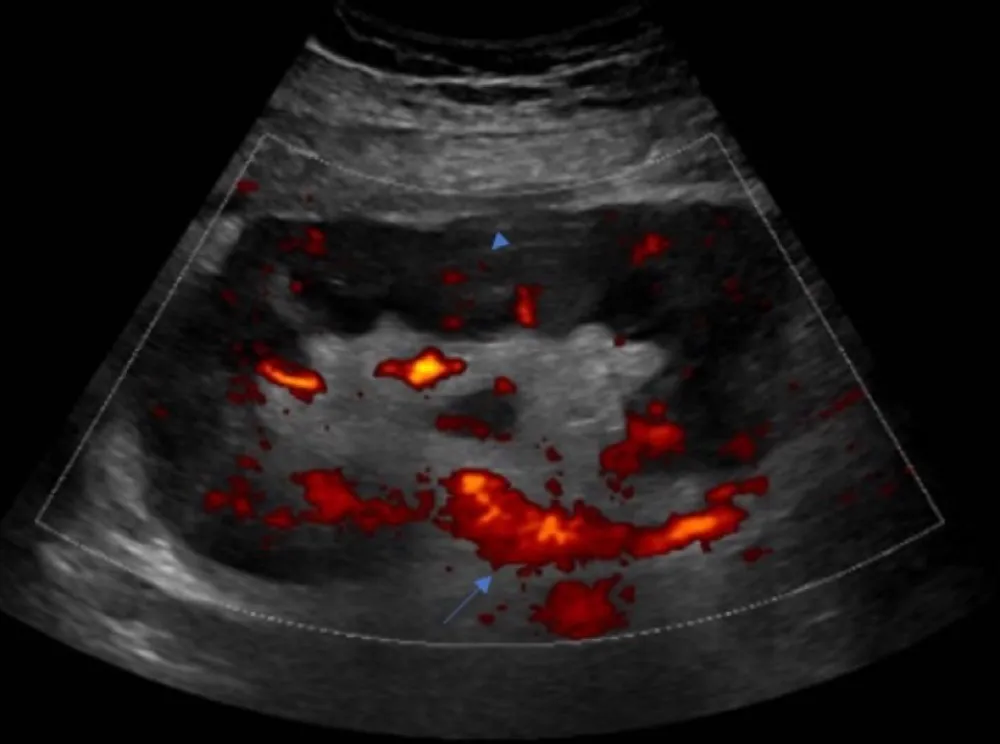

DRC “indeterminada” raramente é falta de diagnóstico — quase sempre é falta de método. Tempo de evolução, urina bem avaliada, USG renal e história clínica dirigida mudam conduta e evitam erros comuns na prática nefrológica.

IRA + Icterícia: Um Caso que Exige Investigação Detalhada